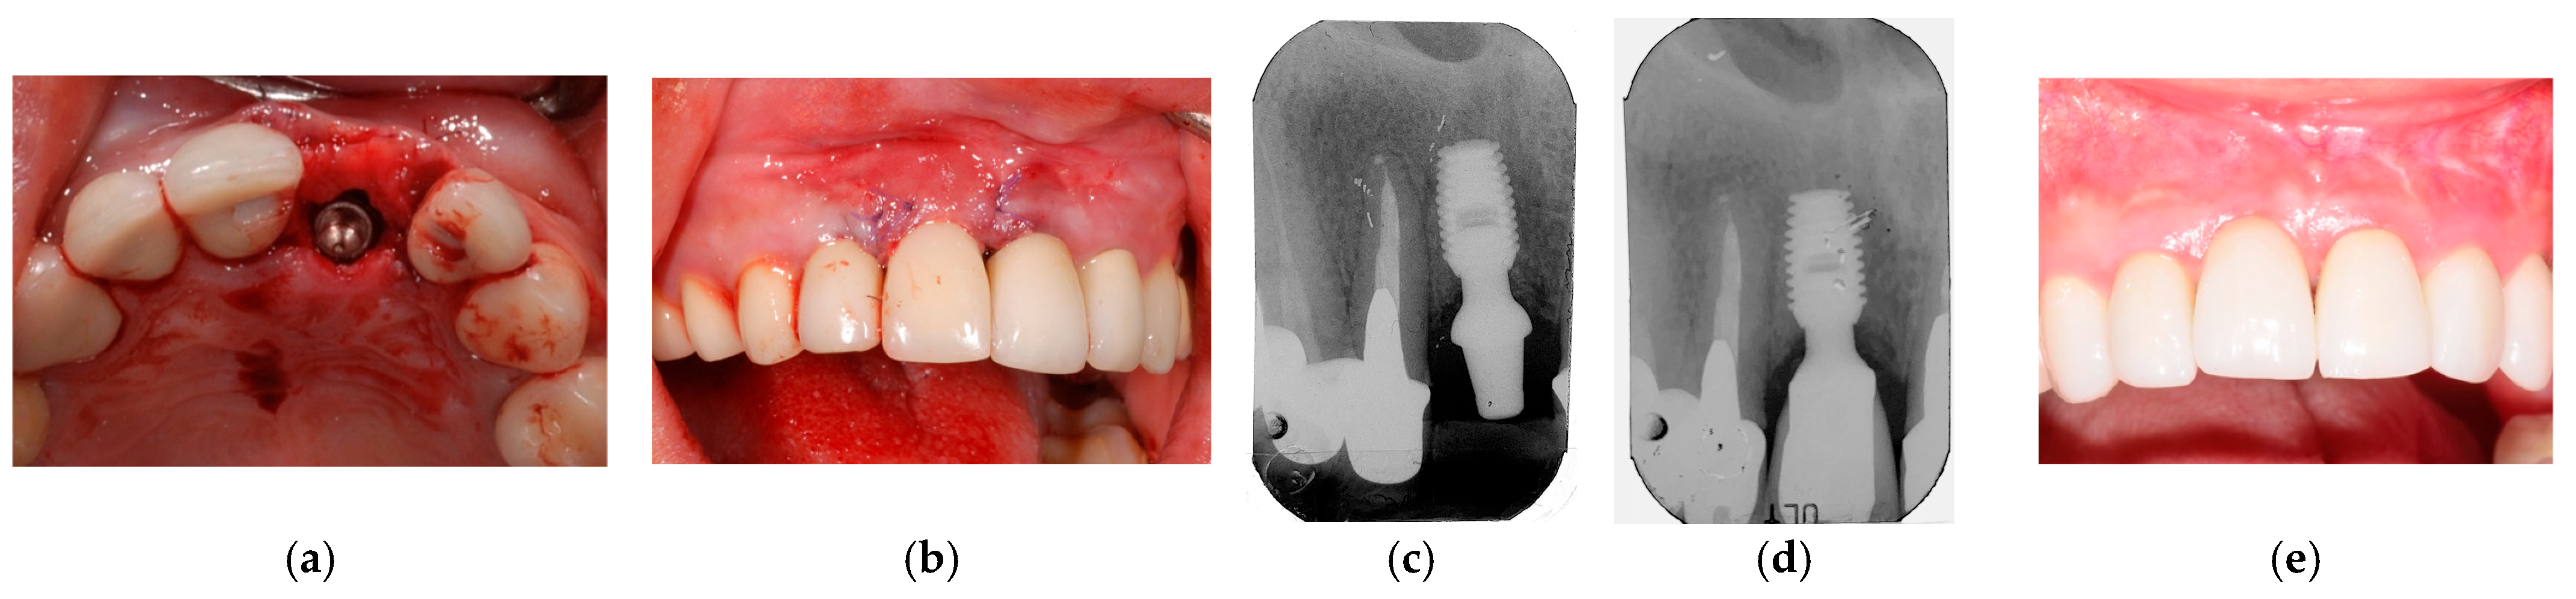

2.9. Clinical Cases and Study Diagram

- Lombardo, G.; Corrocher, G.; Pighi, J.; Mascellaro, A.; Marincola, M.; Nocini, P.F. Esthetic Outcomes of Immediately Loaded Locking Taper Implants in the Anterior Maxilla: A Case Series Study. J. Oral Implantol. 2016, 42, 258–264. [Google Scholar] [CrossRef]